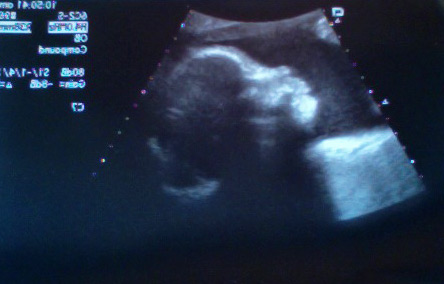

Very cute profile — I think he has my nose.